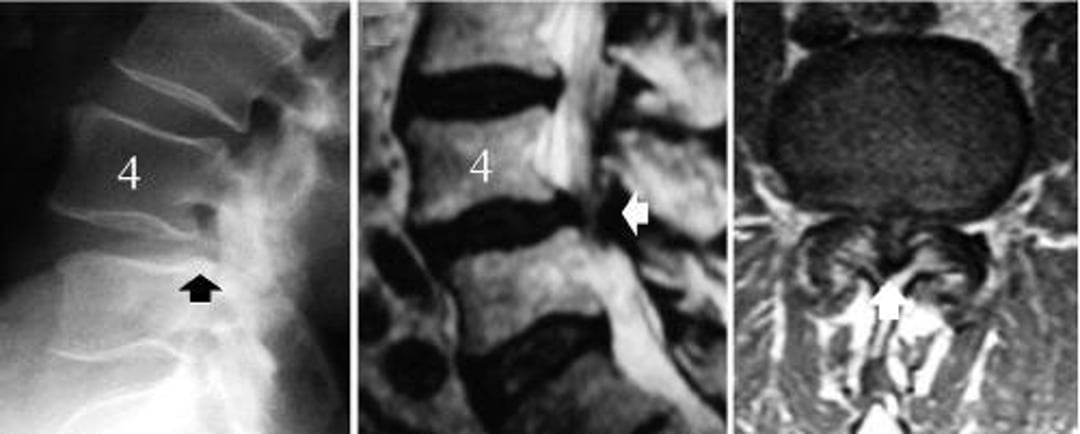

Stenosi spinale lombare causata da spondilolistesi degenerativa di L4-L5

L'immagine a sinistra è una radiografia di profilo della colonna lombare che mostra lo scivolamento della vertebra L4 (freccia nera, il bordo posteriore del corpo vertebrale L5 non è allineato con quello di L4). L'immagine al centro è una scansione RM sagittale mediana che mostra la compressione delle strutture nervose (freccia bianca). L'immagine a destra è una scansione RM assiale che mostra una grave stenosi spinale al livello della spondilolistesi degenerativa, L4-5 (freccia bianca).